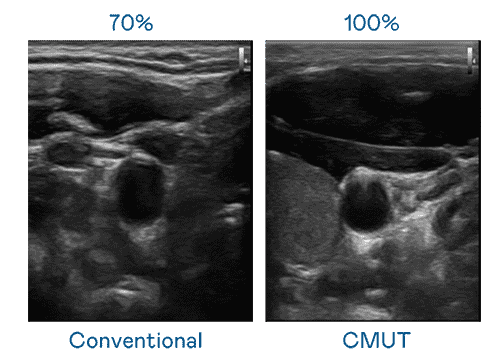

CMUT 技术是一种用电容式微机电元件来产生超音波讯号的技术。。。。与传统 PZT 压电式技术相比,,CMUT 频宽增加 30%,,,更宽频的超音波讯号让影像解析度大幅提升,,是实现高影像品质医疗超音波扫描、、促进精准医疗发展的关键技术。。。。

大频宽带来超清晰影像

超音波影像的解析度高低,,,首先取决于探头能发出的讯号频宽。。。。MG电玩 CMUT 可提供高清晰的超音波讯号,,,,提供高频宽、、高灵敏度、、影像纹理细节更高的超音波影像,,,,协助医护人员缩短影像判读时间及利用精准的医疗影像进行诊断。。。。